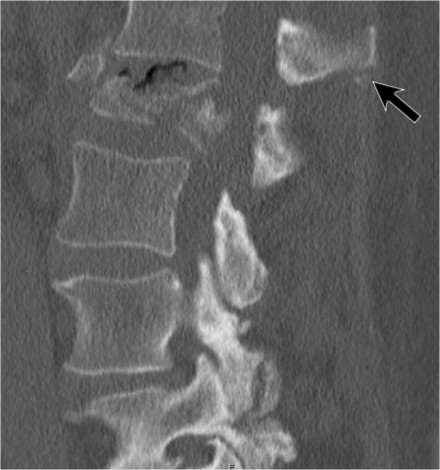

This next case has a great teaching point.

There is widening between the spinous processes.

But there are also little pieces ofbone, that have avulsed at least 10mm away.

At first we thought that little pieces of bone didn't matter, but they

may be the most important sign of a major injury on a CT-scan.

The fact that these little pieces of bone have been so severely displaced means there has to be a major injury.

Now in this case there are lots of other things going on, but sometimes these little pieces of bone are all you get.

If you look back, see how nicely it correlates with the PLC-injury on the MRI.

The teaching point is: pay careful attention to little pieces of bone.